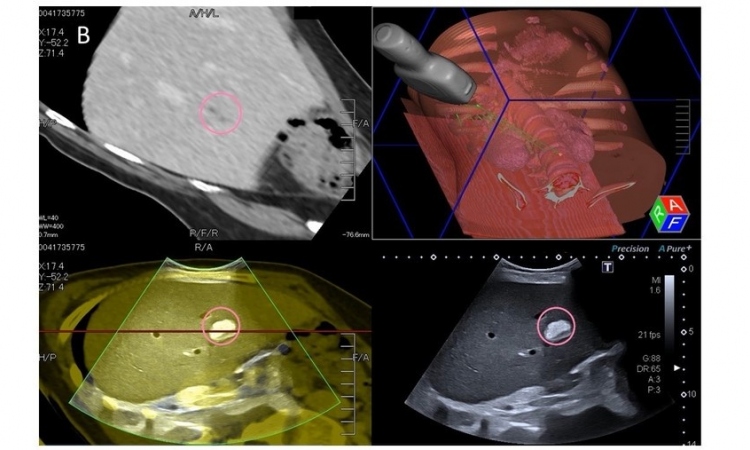

Die Sonografie ist das am häufigsten angewandte Bildgebungsverfahren in der Medizin. Es wird in nahezu jedem medizinischen Fach zur Diagnostik, Therapie und Vorsorge verwendet. Umso wichtiger ist eine professionelle und zuverlässige Anwendung dieses Verfahrens. Für seine hohe Expertise auf diesem Gebiet zeichnete die Deutsche Gesellschaft für Ultraschall in der Medizin (DEGUM) das Uniklinikum Münster als „Interdisziplinäres Ultraschallzentrum“ aus.

In den vergangenen 20 Jahren hat sich die Sonografie-Technik enorm weiterentwickelt und verfügt über ein großes Potential. „Leider hinkt jedoch die flächendeckende gute Ausbildung und eine hochwertige Geräteausstattung vielfach hinterher“, kritisiert Becker. So seien beispielsweise die Sonografie und Kontrastmittel-Sonografie in der Hand erfahrener Anwender die besten und schonendsten Methoden in der Früherkennung von Leberkrebs. Habe der Anwender wenig Ultraschall-Erfahrung, sind andere und teurere Untersuchungsmethoden für den Patienten notwendig. „An diesem Beispiel zeigt sich, dass die Versorgung der Patienten leidet, wenn die fachliche Qualifikation und eine hochwertige Technologie nicht ausgeschöpft werden“, bedauert Becker. „Eine hochqualifizierte Ultraschalluntersuchung ist komplex und erfordert eine gute Ausbildung. Die Zeche für die anderen, wesentlich teureren Untersuchungen zahlt in diesen Fällen dann stillschweigend die Versichertengemeinschaft.“